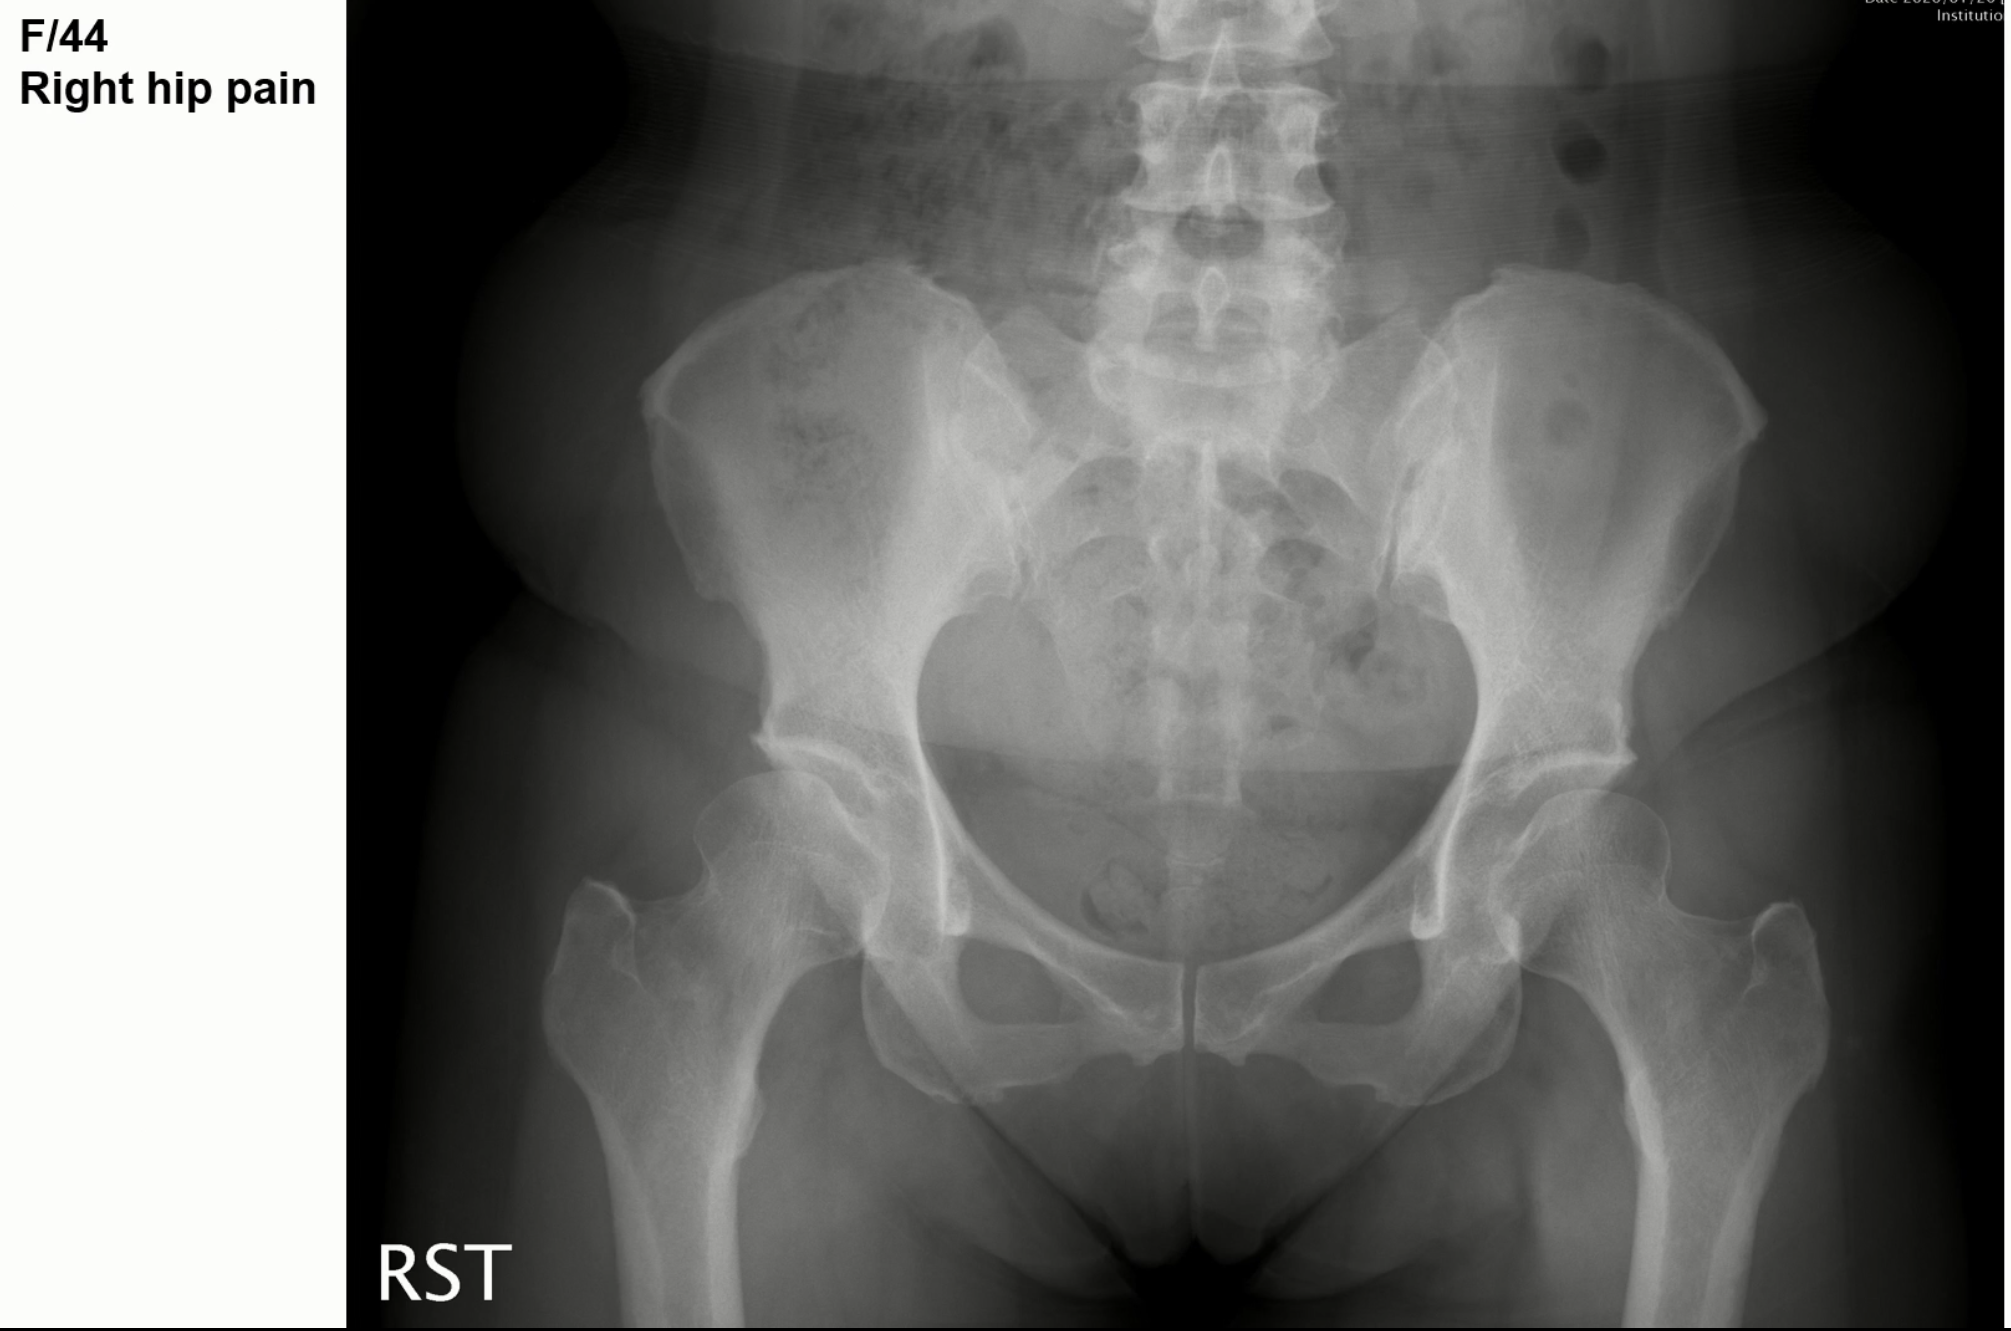

2. 비구이형성증 케이스

엑스레이상 우측 고관절에서 비구 이형성증에 합당한 소견을 보였습니다.